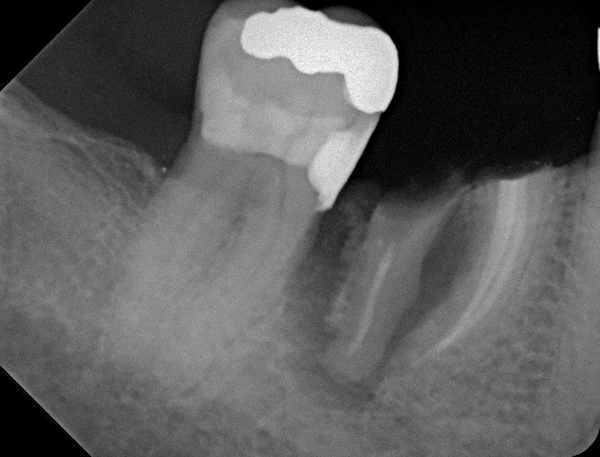

Fig 20. (Case 4) Radiograph of tooth No. 30, which had a hopeless prognosis.

Figure 20

Fig 21. Radiograph of extraction socket. Buccal plate was two-thirds resorbed.

Figure 21